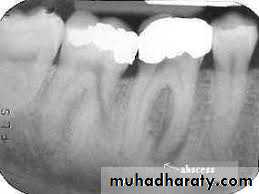

Radiographically, in the acute phase, no signs are observed at the bone (which may be observed 8–10 days later), unless there is recurrence of a chronic abscess, where upon osteolysis is observed.

Radiographic verification of a deeply carious tooth or restoration very close to the pulp, as well as thickening of the periodontal ligament, are data that indicate the causative tooth.

Phoenix abscesses demonstrate the outline of the original chronic lesion, with or without an associated ill-defined bone loss.